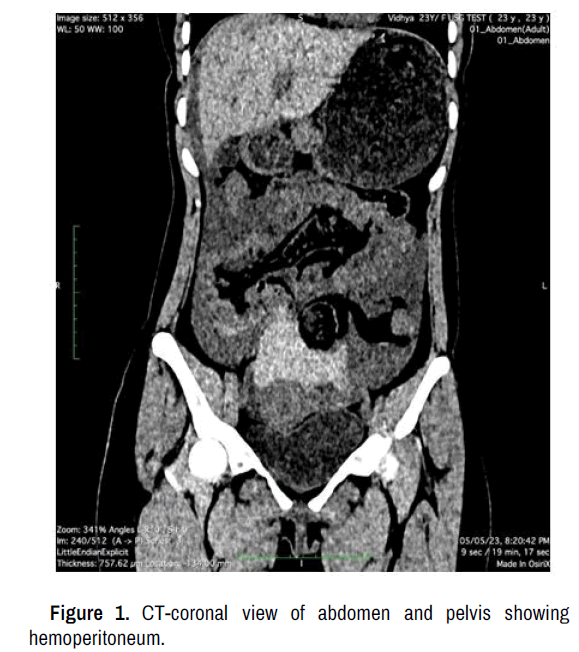

Preoperative laboratory investigation yielded a hemoglobin of 10.1 gm %, total leucocyte count of 16,970/ mm3 and serum beta HCG: 0.21 miu/ml. Diagnostic workup, including ultrasound abdomen with pelvis and CT screening confirmed the presence of moderate to large hemoperitoneum with suspected ruptured corpus luteal cyst (Figures 1-3).

Figure 3. Ultrasound abdomen and pelvis showing hemoperitoneum.

Postcoital hemoperitoneum is an uncommon condition resulting from rupture of an ovarian cyst, typically corpus luteal cyst. Its diagnosis is challenging due to nonspecific natre of symptoms. The presentation can mimic other causes of acute abdomen, such as ruptured ectopic, ovarian torsion. Prompt diagnosis and appropriate management is crucial to prevent severe morbidity and mortality. Clinical observations, laboratory findings and utilization of ultrasound images, CT films provide valuable insights into the diagnosis, surgical planning and assessment of treatment outcomes. Surgical intervention such as laparotomy plays a crucial role in managing post-coital hemoperitoneum when conservative management fails or in severe cases. Surgical approach aims to identify the source of bleeding and achieve hemostasis. Corpus luteum biopsy is performed to confirm diagnosis and assess for any associated pathologies.